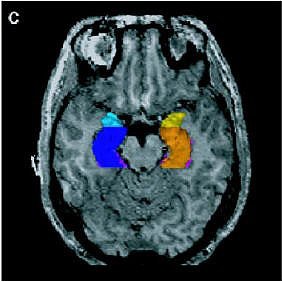

| Above, regions of interest (ROI) examined in MRI study of patients with first-episode schizophrenia or affective psychosis and normal comparison subjects. Top (A) is a 1.5-mm coronal slice of the temporal lobe; the ROI used to evaluate the temporal structures are outlines. The gray matter of the superior temporal gyrus is shown in red (subject left) and green (subject right); more medially, the amygdala-hippocampal complex is shown in orange (left) and blue (right) with the parahippocampal gyrus underneath in pink (left) and purple (right). Below, a left lateral view of a 3D reconstruction of the cortical surface with the anterior superior temporal gyrus (light pink) and posterior superior temporal gyrus (red). |

![]() |

| Same subject. Above and below, axial MRI is used to present top-down views of the 3D reconstruction of the amygdala-hippocampal complex and parahippocampal gyrus. All images: Figure 1, Hirayasu Y, Shenton ME, Salisbury DF, et al. "Lower Left Temporal Lobe MRI Volumes in Patients with First-Episode Schizophrenia Compared with Psychotic Patients With First-Episode Affective Disorder and Normal Subjects," (Am J Psychiatry 1998; 155:1384-1391). |